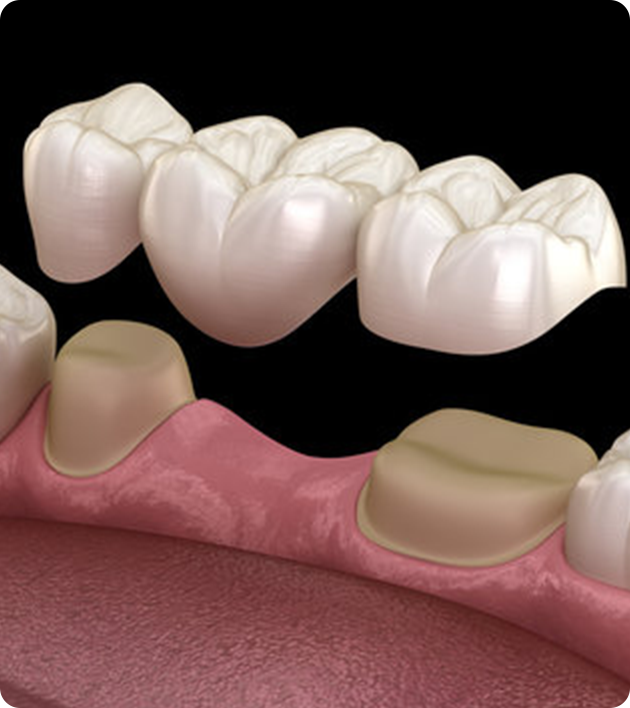

A dental bridge replaces one or more missing teeth by anchoring artificial teeth (pontics) to the surrounding natural teeth or implants. It restores your ability to chew and speak properly while improving your smile’s appearance.

Types of Dental Bridges

1. Traditional Bridge:

• How it works: Uses crowns placed on both sides of the missing tooth to hold the pontic.

• Best for: Patients with healthy teeth on either side of the gap.

1. Tooth Preparation: Neighboring teeth are reshaped for crowns (if needed).

2. Impression or Scan: Taken to ensure a perfect custom fit.

3. Temporary Bridge: Placed to protect the area while the final bridge is being fabricated.

4. Final Placement: The custom bridge is cemented or bonded securely in place.